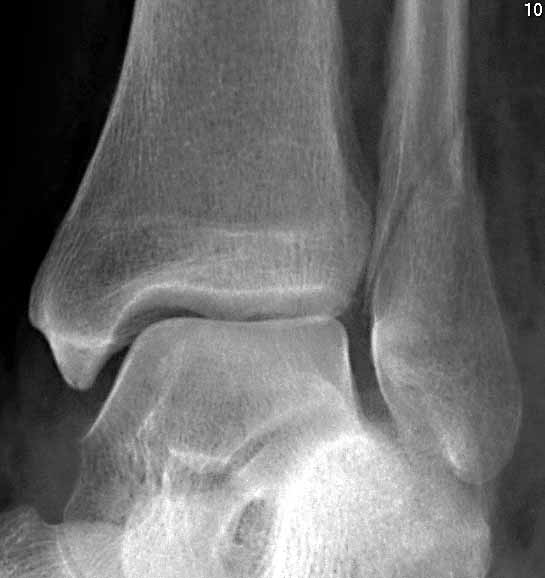

From radiopaedia.org

Ankle fracture er B Image er B Fracture Moon Boot the boot you have been given is not needed to aid fracture healing but will help with your symptoms and should be worn whenever you’re walking. if your injury is classified as a stable weber b type fracture, you will be treated in a boot. treatment can be nonoperative or operative depending on fracture displacement, ankle stability,. er B Fracture Moon Boot.